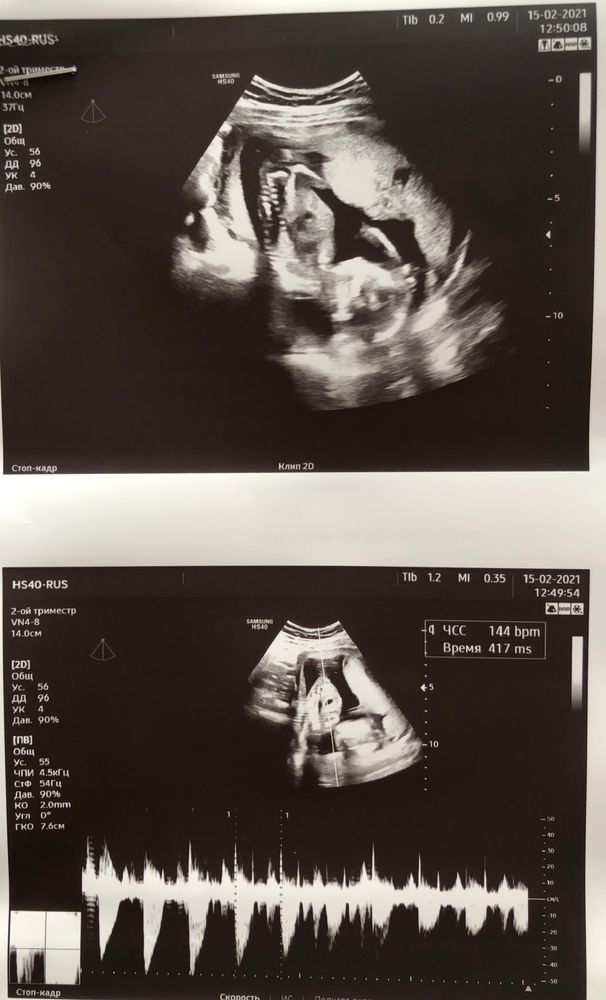

Узи 15+6 недель☺️

Сходили на узи, тянул бок, оказалось связки. Малышка лежит головой вниз, видимо, так нравится:)